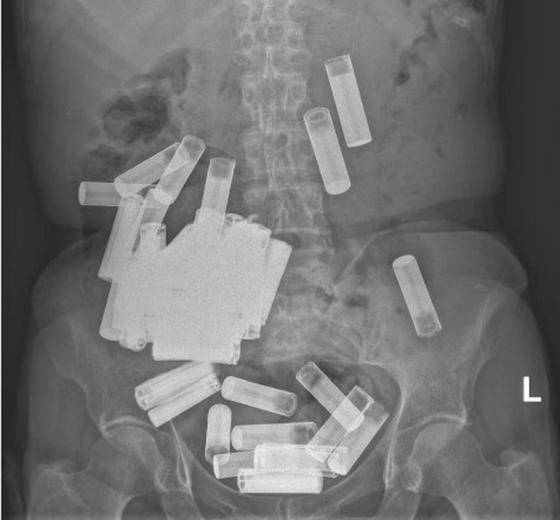

아일랜드의 한 66세 여성의 뱃속에서 무려 55개에 달하는 건전지가 발견돼 충격을 주고 있다.

의료진은 엑스레이 촬영을 통해 A 씨 배 안에 수십 개의 건전지가 있던 것을 확인했다.

A 씨는 55개의 건전지를 삼켜 세인트 빈센트 대학병원 응급실로 내원했다. 의료진은 엑스레이 촬영을 통해 A 씨 배 안에 수십 개의 건전지가 있던 것을 확인했다.

의료진은 A 씨가 장폐색이나 위장 천공 등의 징후를 보이지 않아 비수술 치료를 권했다. 이에 A 씨는 일주일간 5개의 AA 건전지를 대변으로 배출했다. 하지만 나머지 건전지는 위장에 끼어 배출되지 못했다고 한다.

이후 A 씨가 복통과 식욕부진 등을 호소하기 시작하자 의료진은 개복수술 등을 통해 남은 건전지를 제거했다. 당시 A 씨의 위는 건전지 무게 탓에 치골까지 늘어났던 것으로 전해졌다.

의료진 측은 저널을 통해 "고의적인 자해의 한 형태로 여러 개의 건전지를 의도적으로 삼킨 것은 이례적"이라며 "현재까지 건전지 삼킴 사고로 보고된 것 중 가장 많은 건전지를 삼킨 사례"라고 밝혔다.